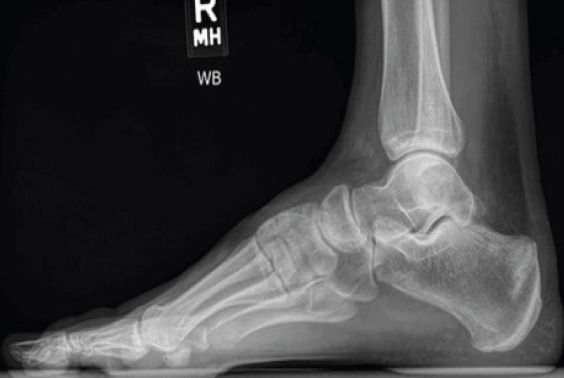

Introduction: Although uncommon, the calcaneus stress fracture is an important differential diagnosis of both traumatic and non-traumatic foot pain. The calcaneus is one of the tarsal bones that are prone to stress fractures, which usually occur as a result of overuse. The diagnosis of stress fractures is aided by plain radiographs, with the mainstay of management usually conservative.

Case report: This case report is of a 57-year-old female who presented with instant left-sided heel pain after stepping off a step at home. Investigations included plain radiographs of the left foot and ankle, with no obvious fractures visible. As a result, a magnetic resonance imaging was obtained, which confirmed a stress fracture of the left os calcis. Management remained conservative, with the patient placed in an ankle boot for 4-6 weeks with non-weight bearing instructions provided. Heel pain can be caused by a stress fracture of the calcaneus, and although these injuries are usually caused by repetitive forces, this case study provides a reminder that they can also be caused by acute trauma.

Conclusion: Calcaneal stress fractures, typically due to overuse, can also result from acute trauma and may require MRI for diagnosis when plain radiographs are inconclusive. The mainstay of treatment is conservative management.